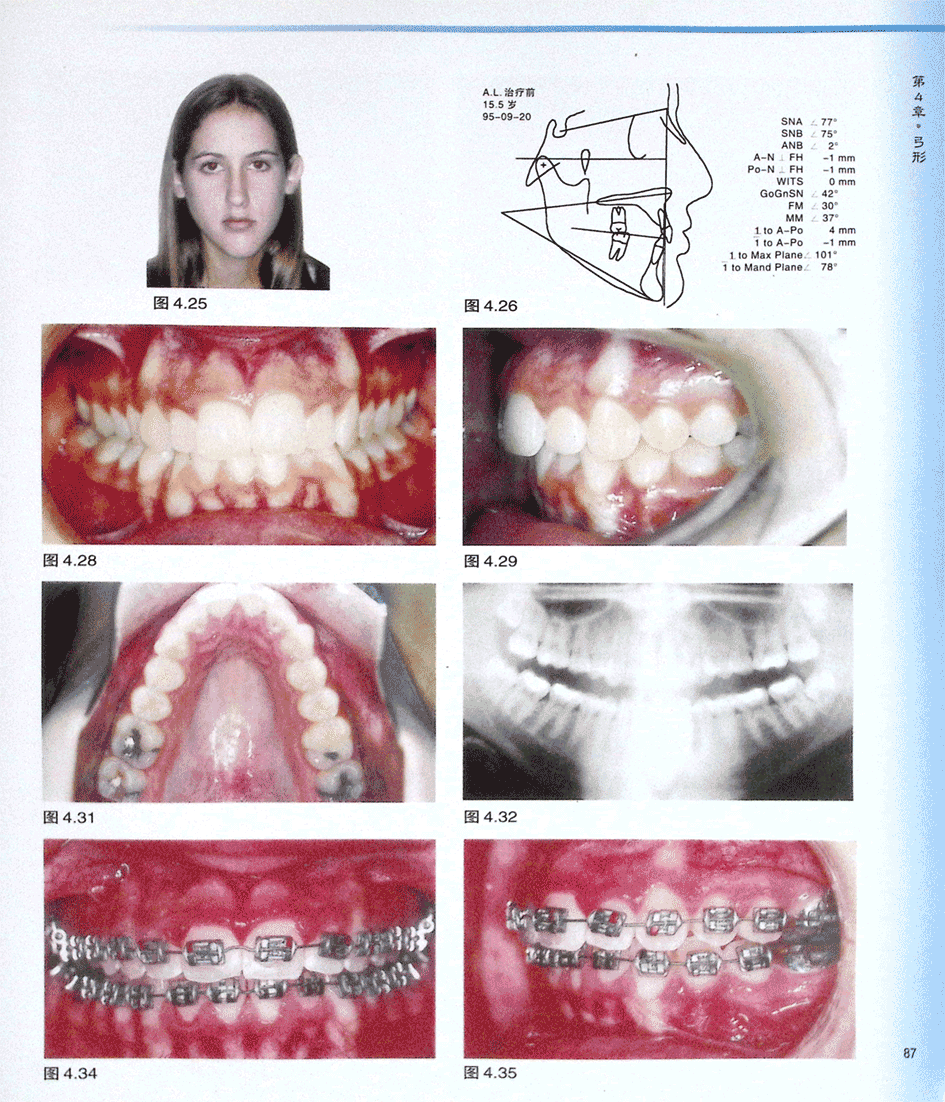

病例AL(一)